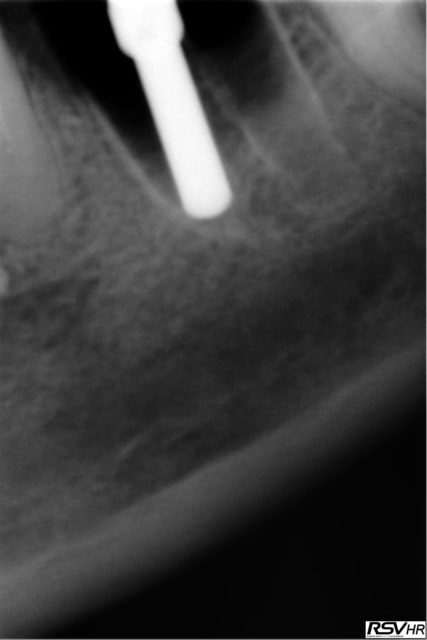

Un dernier pour la route legacy2 7mm

16 RTE 2006 /2007 avec curetage périapical et IRM

échec de cicatrisation et extraction-implantation le26.02.2011

empreinte essayage pose le 24.10.2011

radios de contrôle en 2012 et 2013

patiente revue en 2014 cbct =ok